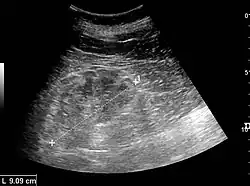

Ultrasound

Kidney ultrasonography is useful for diagnostic and prognostic purposes in chronic kidney disease. Whether the underlying pathologic change is glomerular sclerosis, tubular atrophy, interstitial fibrosis, or inflammation, the result is often increased echogenicity of the cortex. The echogenicity of the kidney should be related to the echogenicity of the liver or the spleen. Moreover, decreased kidney size and cortical thinning are often seen, especially when the disease progresses. However, kidney size correlates to height, and short persons tend to have small kidneys; thus, kidney size as the only parameter is unreliable.[63]